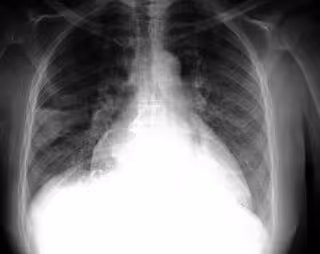

Patología pulmonar

FLICKR/PULMONARY PATHOLOGY/CC BY-SA 2.0